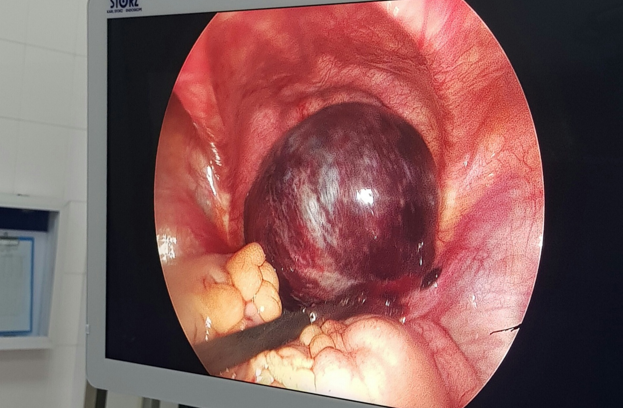

Hình 1: U buồng trứng xoắn hoại tử

U buồng trứng ở trẻ em là bệnh thường gặp nhưng lại hay bị bỏ qua do triệu chứng của bệnh khá mơ hồ khiến gia đình bệnh nhân chủ quan và hay đưa trẻ đến khám lúc u quá to hoặc có biến chứng xoắn u, gây hoại tử một bên buồng trứng và vòi trứng, ảnh hưởng đến khả năng sinh sản sau này của trẻ.